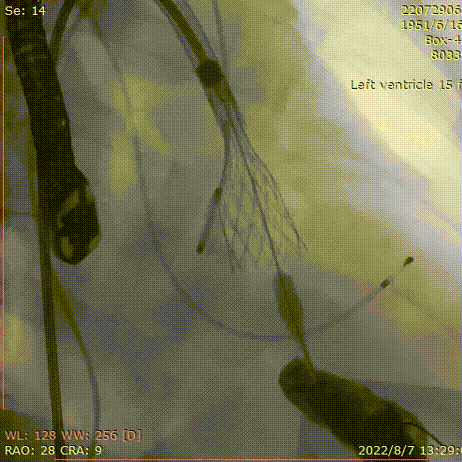

手术过程

20mm球囊预扩张:

球囊有明显腰征,无漏。

术后造影:

大鞘撤出外周血管,造影

术中20mm球囊预扩可见明显腰征,无瓣周漏,左冠充盈速度可。选择TaurusElite  AV23瓣膜送至主动脉弓,输送系统轻松过弓及跨瓣,精准定位无冠窦最低点,利用可回收功能,术中对位置进行适当调整,大大提升了瓣膜精准释放的几率,保证了手术的安全性。

TaurusElite AV23瓣膜经过2次调整之后,第3次释放定位位置接近瓣环,心脏瓣膜团队精确定位,零位释放,瓣膜在术前评估的位置牢牢锚定!整个手术过程连贯如行云流水,团队配合默契,操作细致熟练,主动脉根部造影及即时食道超声提示无瓣周漏,TaurusElite首秀成功!